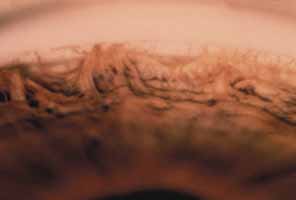

The second form of isolated trabeculodysgenesis has a concave iris insertion. The plane of the iris is posterior to the scleral spur. However, the anterior stroma continues over the trabecular meshwork, obscuring the scleral spur and ending just posterior to Schwalbe's line (Fig. 2).

Fig. 2 Concave iris insertion in trabeculodysgenesis. Superficial iris tissue wraps around the angle recess and covers the internal surface of the trabeculum. This may take the form of dense sheets (left) or an arborizing network (right). This is different from the small processes seen in the anterior iris insertion. (Hoskins HD Jr, Shaffer RN, Hetherington J: Anatomical classification of the development of glaucomas. Arch Ophthalmol 102:1331, 1984. Copyright © 1984, American Medical Association.)